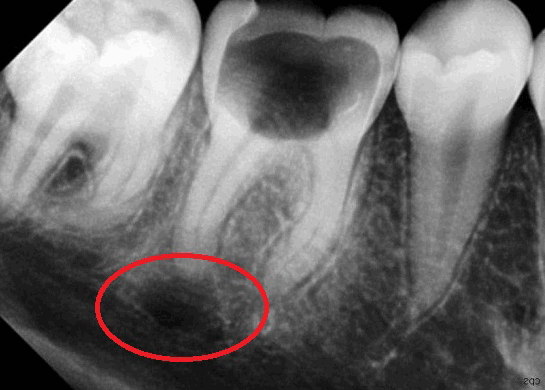

Как правило, киста зуба обнаруживается абсолютно случайно – во время профилактического осмотра или лечения соседнего зуба. Заболевание выявляется рентгенологически.

На снимке видно круглое темное пятно, имеющее четкие контуры, располагается у верхушки корня зуба (окружает его в виде «нимба»). Если у доктора сомнения насчет того, опухоль это или киста, он отправляет пациента на пункцию кисты. В этом случае киста прокалывается, иглой делается забор жидкости и она проходит гистологическое исследование на принадлежность клеток к раковым.